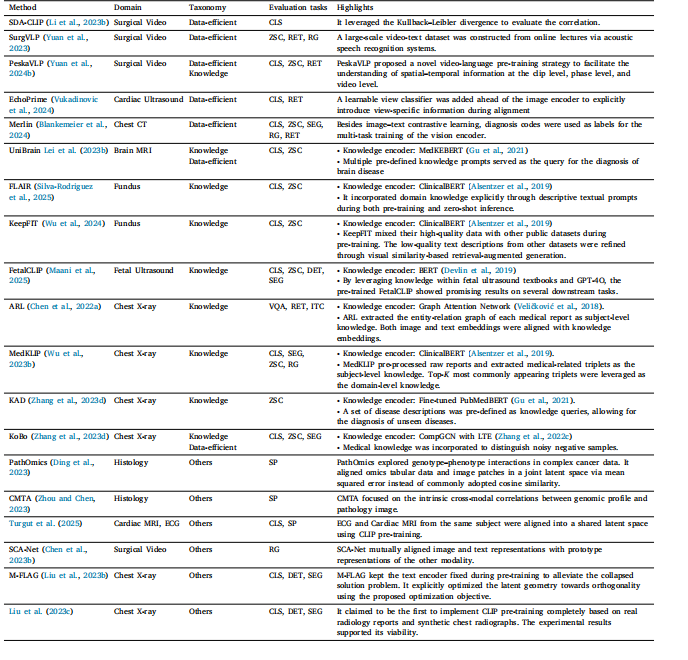

Table 2Overview of representative studies focusing on improving CLIP pre-training framework. CLS: classification; ZSC: zero-shot classification; SEG: segmentation; DET: detection; RET:retrieval; VQA: visual question answering; PG: phrase grounding; RG: report generation; ITC: image–text classification; SP: survival prediction.

表2 专注于改进对比语言-图像预训练模型(CLIP)预训练框架的代表性研究概述。CLS:分类;ZSC:零样本分类;SEG:分割;DET:检测;RET:检索;VQA:视觉问答;PG:短语定位;RG:报告生成;ITC:图像-文本分类;SP:生存预测。